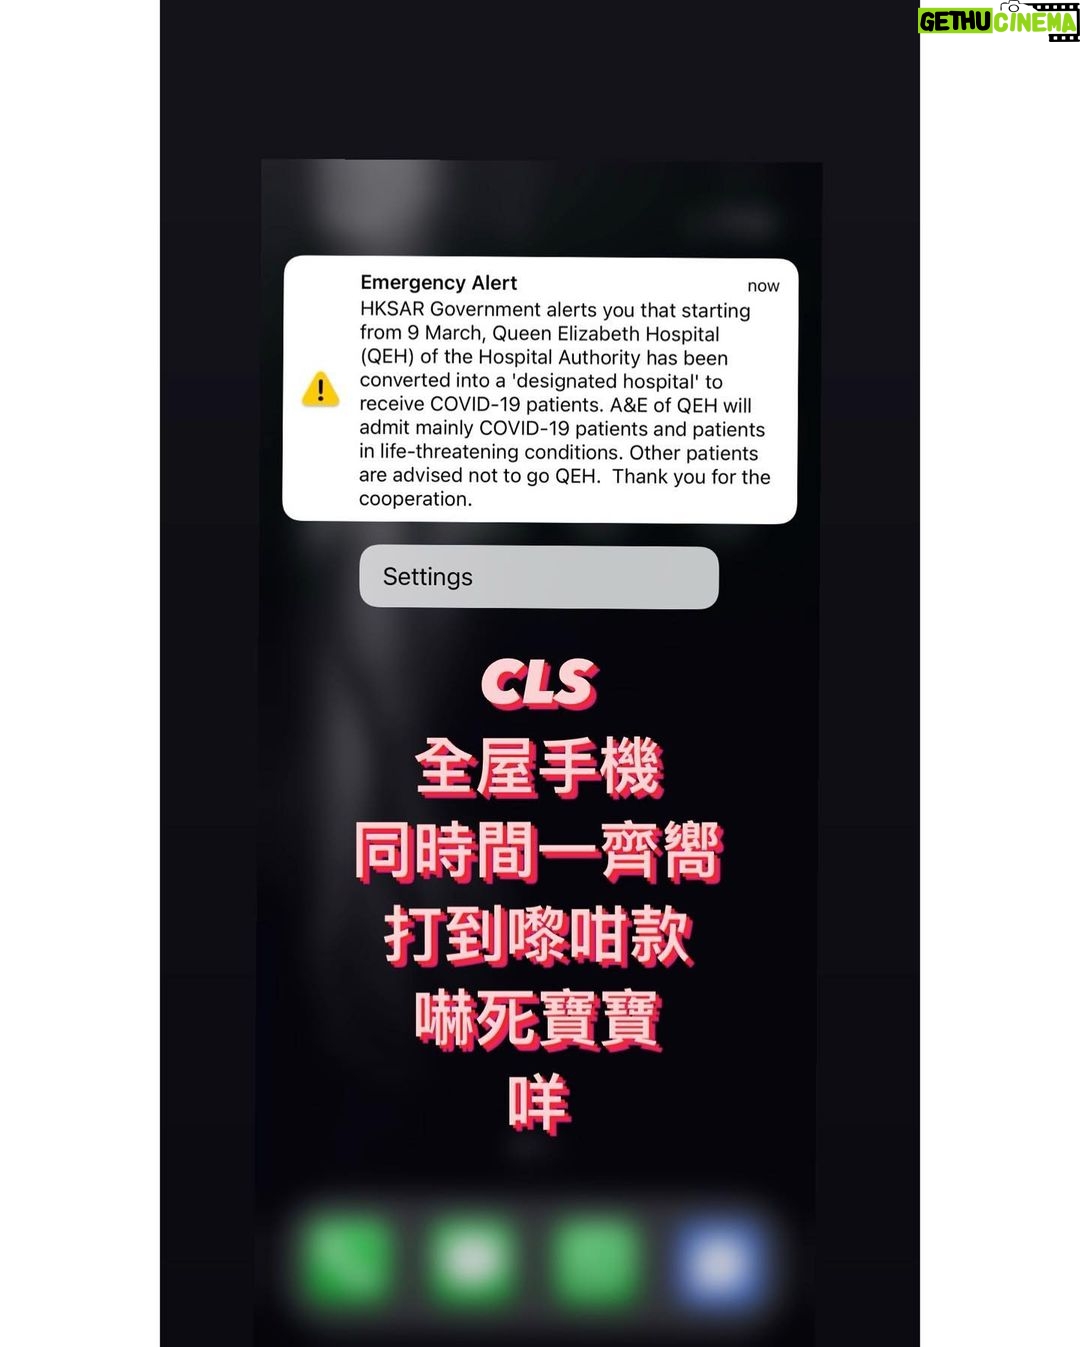

1.8K Likes – Bonnie Chiu Hok-Yee Instagram

Caption : 曲你個乖 嚇到個心離晒罩喎 我倆老以為自己有幻覺 :咩聲呀 :係咪地震警報? :我哋中咗感冒? 虎你咩!Likes : 1750